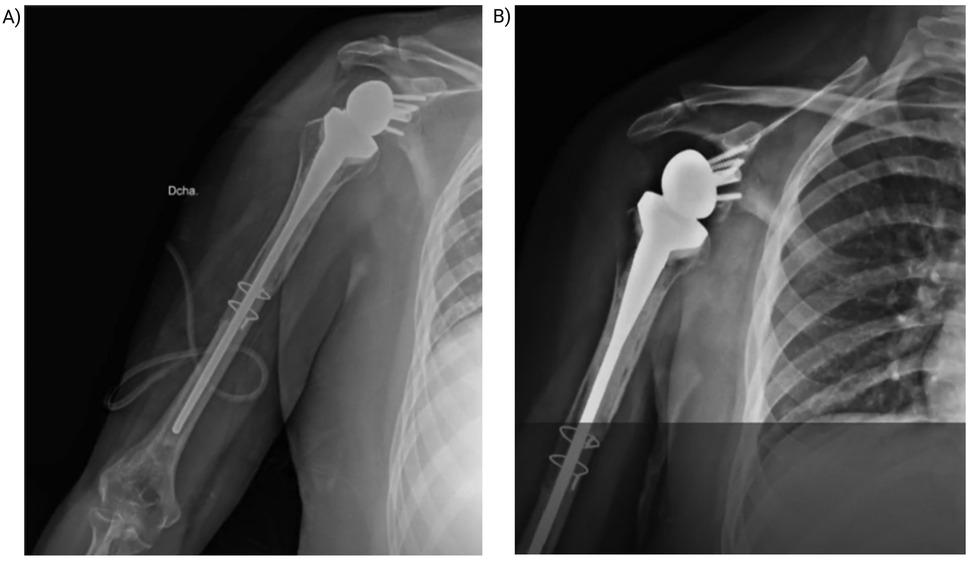

At the 3-month postoperative visit, the patient showed a well-healed surgical scar, no radiographic evidence of recurrence, and improved ROM. Repeat imaging and functional assessment were scheduled for 3 months later to monitor recovery and exclude recurrence (Figure 3).

Figure 3

X-rays showing a shoulder prosthesis. Image A depicts an implant in the humerus and shoulder joint with accompanying pins and wires. Image B shows another view of the same prosthesis, highlighting the artificial ball and socket joint.

Figure 3. Postoperative control and follow-up. (A) Immediate postoperative radiograph showing reverse shoulder prosthesis with cerclage wire and “flute-beak” osteotomies. (B) Radiograph at 5 months postoperative demonstrating early osteointegration at the graft-host interface.

At the most recent follow-up, the patient reported substantial clinical improvement and enhanced quality of life. Examination of the right shoulder showed: flexion 90°, abduction 90°, adduction 10°, extension 10°, internal rotation 50°, and external rotation 50°. Strength was graded 4/5, sensation 1/2, and deep tendon reflexes 1/4. The surgical site remained clean and dry, without signs of infection or inflammation. Rehabilitation is ongoing, focusing on muscle strengthening, proprioceptive training, and isometric and isotonic exercises to further restore function (Figure 4).